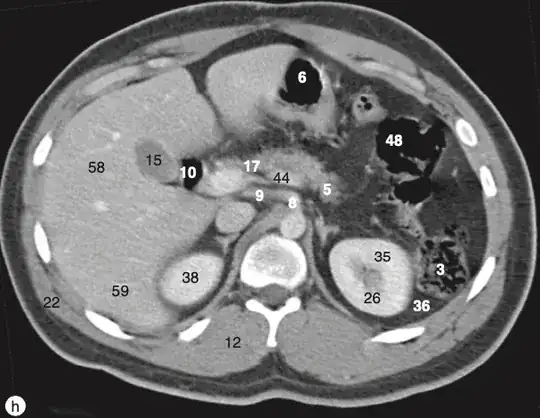

How do we differentiate the the truncus coeliacus from the superior mesenteric artery when looked at from an MRI in the axial plane? For example, the images that I attached, how can I differentiate 8 from 51? I cannot see a difference. (Source of images: Imaging atlas of human anatomy, Weir & Abrahams')

Looking at this diagram, the coeliac trunk itself bifurcates shortly after branching from the aorta. The SMA moves inferiorly and anteriorly in a more straight path. This would make 51 the SMA and 8 the coeliac trunk. This would fit with the liver appearing smaller at the more inferior level of the SMA.

Actually I’m going to make an edit. Disclaimer - I’m not sure how accurate this is, but it seems coeliac trunk moves to the right shortly after branching from the aorta. The SMA moves inferiority and anteriorly in a more straight path. This would make 51 the SMA and 8 the coeliac trunk. This would fit with the liver appearigg by smaller at the more inferior level of the SMA. – Chris Dec 01 '23 at 20:46